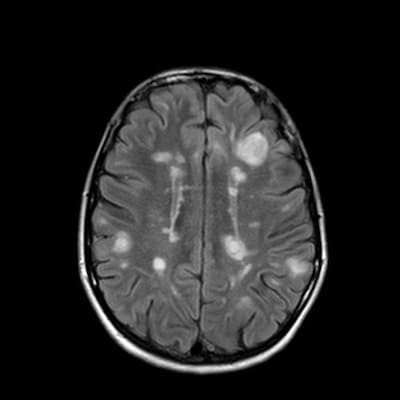

Миндалины мозжечка располагаются выше большого затылочного отверстия . Заключение: МРТ картина последствий перенесенного менинго-энцефалита в виде кистозно-глиозных изменений в обоих полушариях большого мозга .